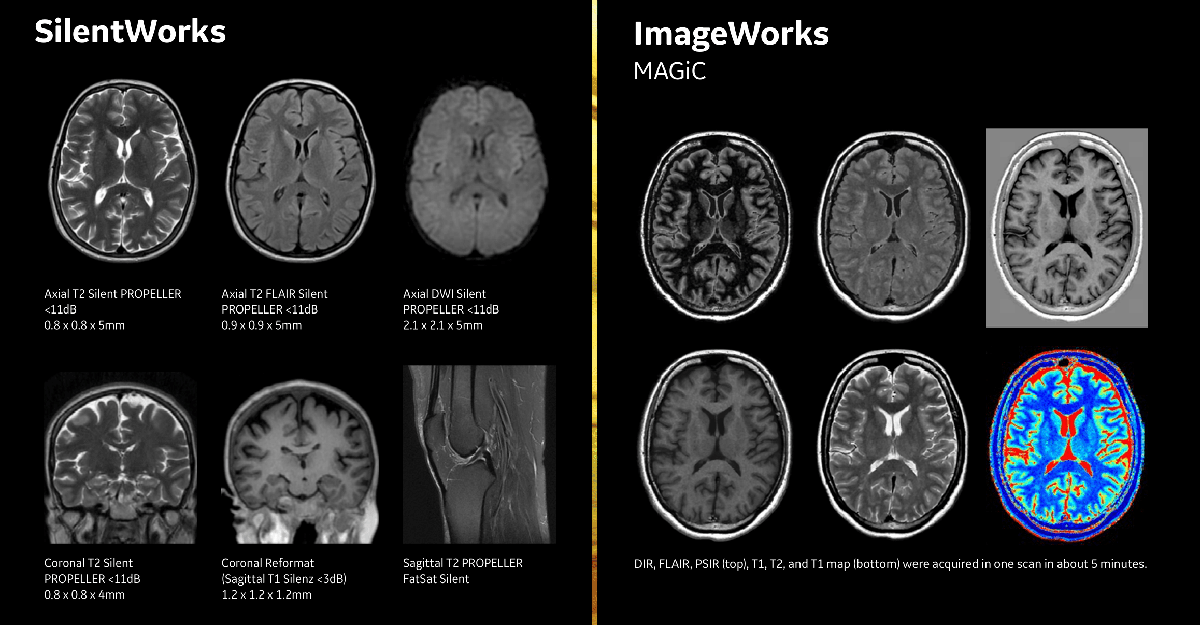

SilentWorks

Технология шумоподавления от GE Healthcare, которая помогает создать максимально комфортные условия для пациента. Стандартное МР-сканирование по громкости сравнимо с рок-концертом, но инновационная технология SilentWorks снижает шум для большинства видов последовательностей практически до уровня шума окружающей среды.

ImageWorks

ImageWorks повысит производительность МРТ. Всего лишь одно сканирование с помощью MAGiC обеспечит вас визуализацией высокого качества, а постобработка с READY View — последовательными и четкими результатами.